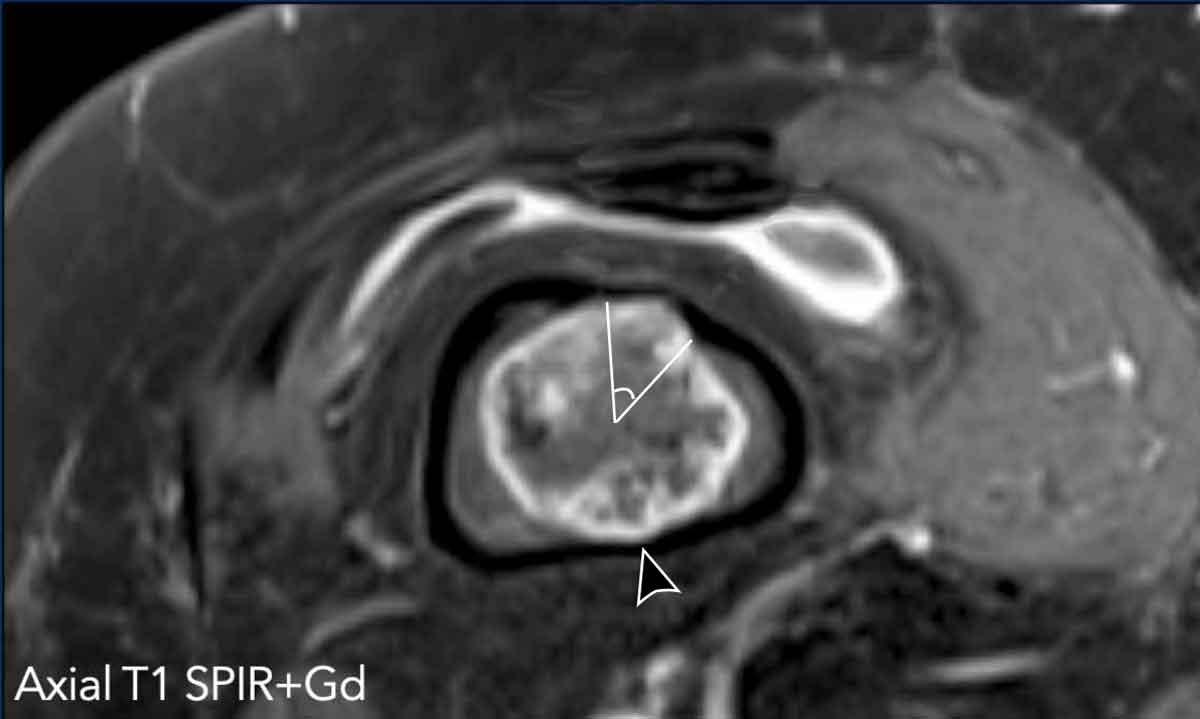

Hình gợn sóng vỏ xương (Scalloping)

Các khối u sụn có thể gây ra hình gợn sóng vỏ xương, biểu hiện là hình ảnh tiêu xương rõ nét lan rộng từ khoang tủy xương.

Nhóm nghiên cứu Birmingham đề xuất

tiêu chí BACTIP để đánh giá MRI các khối u sụn và hướng dẫn chuyển tuyến đến

trung tâm chuyên khoa cấp cao hoặc kết thúc theo dõi.

BACTIP định nghĩa hiện tượng xói mòn vỏ xương là

khu trú khi phần chu vi tổn thương bị ảnh hưởng dưới 10%, được đo

trên lát cắt trục ngang có đường kính khối u lớn nhất.

Trong khi đó, hiện tượng xói mòn vỏ xương trên 10%

chu vi tổn thương được định nghĩa là lan rộng.

Ý nghĩa của mức độ sâu của hiện tượng xói mòn vỏ xương

vẫn chưa được làm rõ.

Hình ảnh

Ảnh T1 SPIR trục ngang sau tiêm thuốc cản từ cho thấy hình ảnh lõm vỏ xương ở phía trước trên khoảng 43/360 độ.

Điều này có nghĩa là lõm vỏ xương chiếm 12% chu vi khối u (mức độ rộng).

Cũng lưu ý hình ảnh lõm vỏ xương phía sau kín đáo hơn (đầu mũi tên).

Khối u này cho thấy hình ảnh ngấm thuốc dạng vách-nốt, ngoại vi.

Lưu ý các vùng tín hiệu thấp phù hợp với hình ảnh vôi hóa.